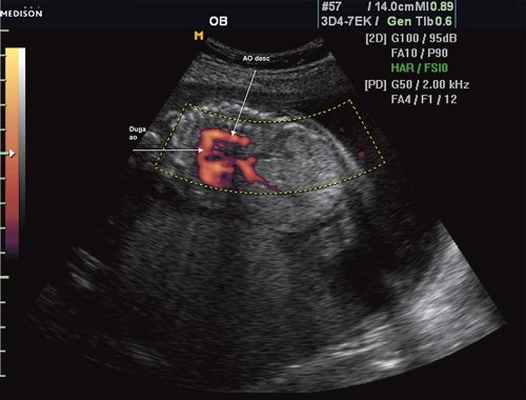

Рис. 1. Восходящий отдел, дуга и нисходящий отдел аорты плода в режиме энергетического допплера в норме.

Согласно "теории дуктальной ткани" коарктация аорты возникает в результате миграции гладких мышечных клеток протока в предуктальную аорту, с последующей констрикцией и сужением просвета аорты [4]. При формировании коарктации аорты в области перешейка сохраняется сужение различной протяженности и формы (рис. 2, 3). Наиболее часто это проявляется в виде локальной перетяжки, выше или ниже которой диаметр аорты сохраняется в норме.

Рис. 2. Ультразвуковое исследование восходящего отдела, дуги и нисходящего отдела аорты. Стрелкой указано место сужения.